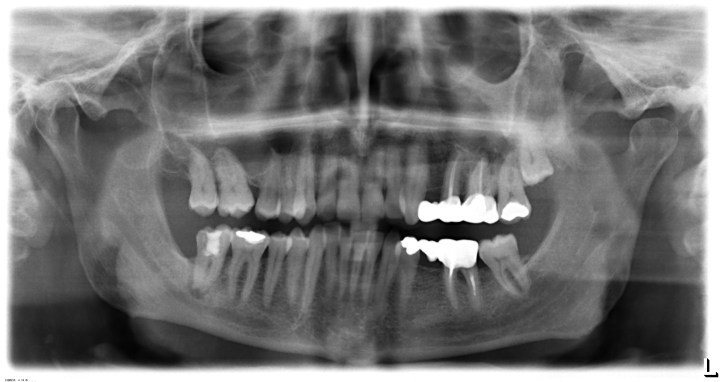

Più di una roulette russa. Una bomba ad orologeria, in bocca, tra i denti, pronta ad esplodere per meccanismi chimici perversi: gli amalgami, le otturazioni in gergo ‘piombate’ in uso da 150 anni per curare le carie, possono trasformarsi in una minaccia per la salute. Nonostante la sindrome dei metalli pesanti per molti, anche nella comunità scientifica e tra gli odontoiatri, sia ancora un controverso rompicapo, addirittura c’è chi la nega, l’evidenza di una vita migliore con denti ‘metal free’ è però innegabile.

L’amalgama, miscelazione alchemica di una componente liquida e solida, è composta dal 50% di mercurio e per il resto un terzo equamente diviso tra argento, rame e stagno (a volte zinco). Col passare del tempo piccole correnti elettriche ionizzanti (elettrogalvanismo) intensificate anche dall’elettrosmog di cellulari perennemente all’orecchio (cioè attaccati alla bocca) potrebbero migrare dalle otturazioni nel cavo orale verso l’interno del corpo e nel sangue mentre mastichiamo, respiriamo e beviamo.

Così il vapore di mercurio, metallo altamente cancerogeno, è rilasciato in media 30mg al giorno e i suoi depositi, dalla radice del dente, calano fino all’osso mandibolare, insidiando cuore, colon, pancreas e persino il cervello (supera la barriera emetoencefalica!), da cui i sintomi tipici del mercurialismo e per le donne incinte persino la trasmissione al feto per via della placenta e poi al neonato nel latte.